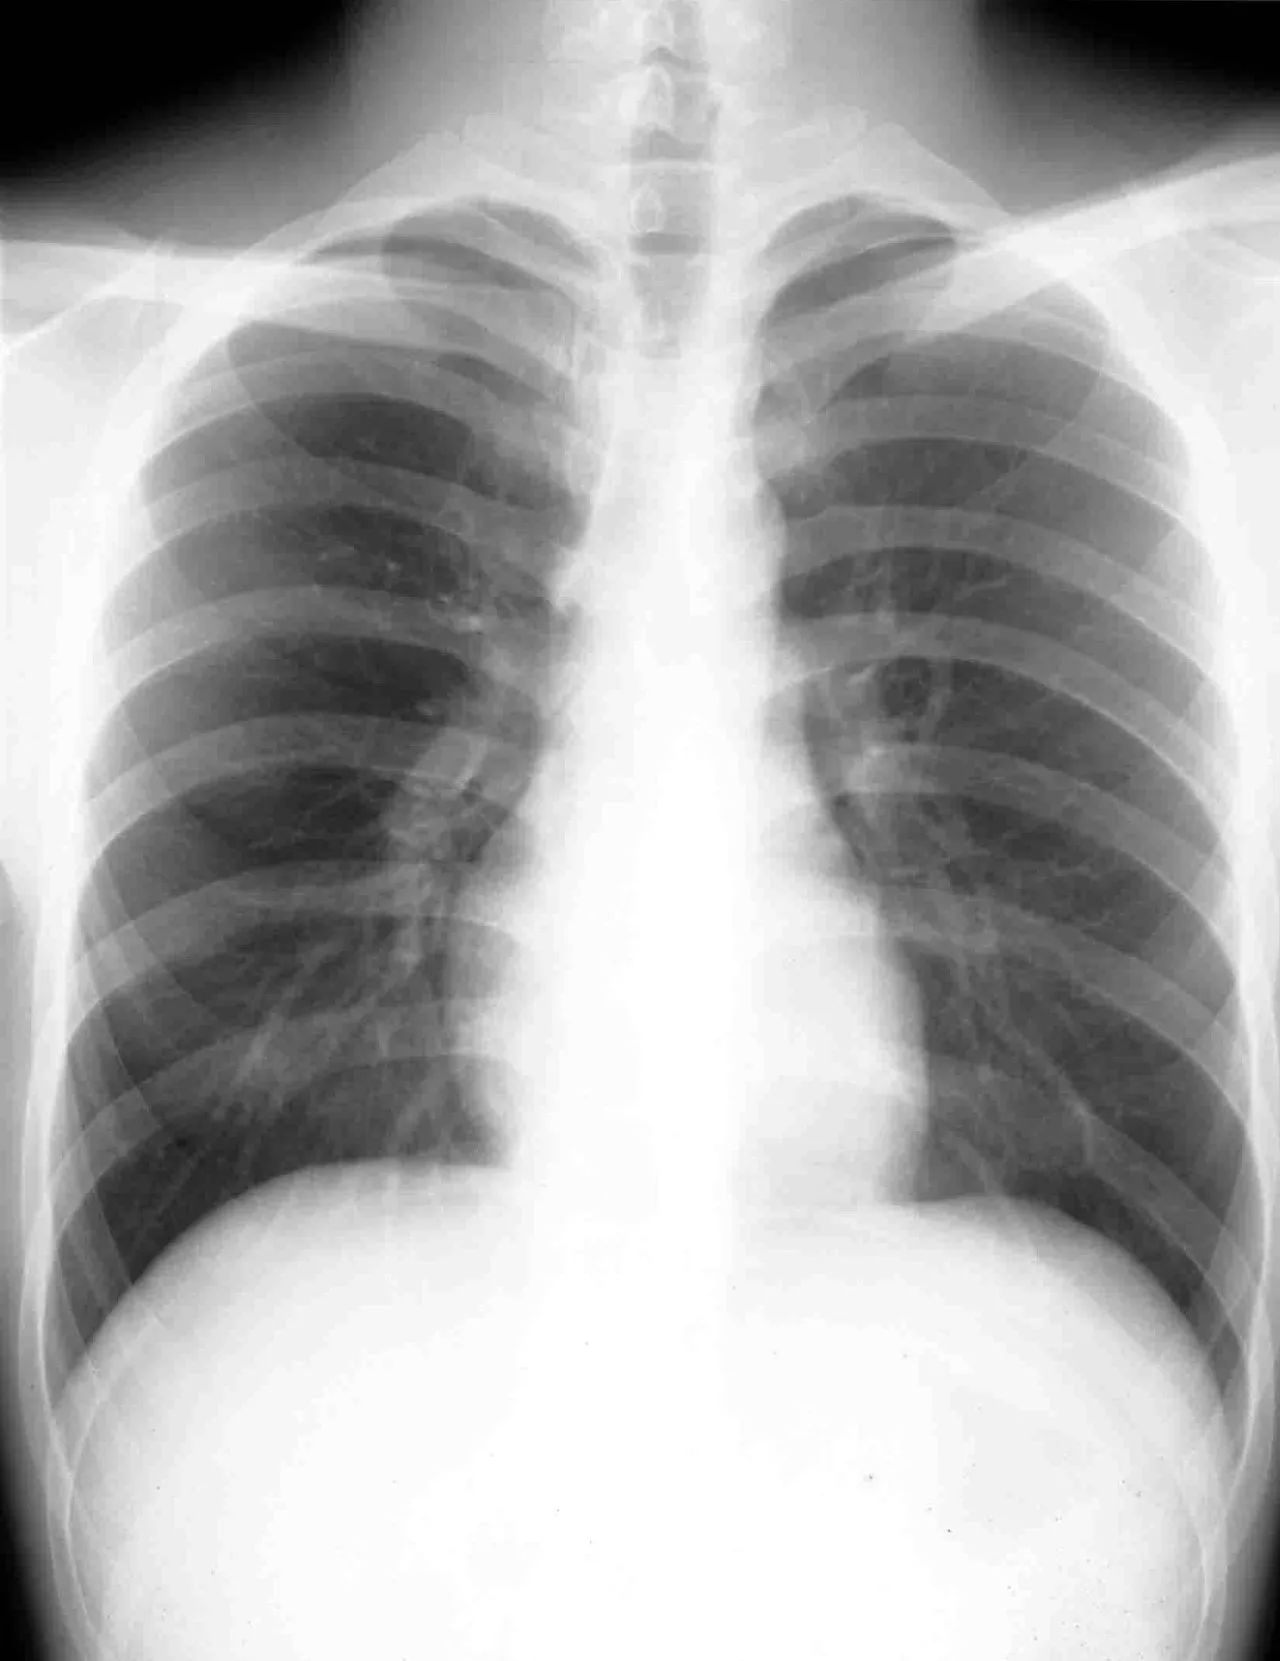

X线胸部摄影,前后重叠图像

众所周知,到医院去做普通的X光检查后,拿到的片子上所看到的影像,是*体器人官**组织的重叠影像,不是前后重叠,就是左右重叠,很多病变就有可能被掩盖而出现漏诊。而体层摄影,也称断层摄影或分层摄影,就是通过一些机械装置,可以设定焦点层面,将X光按一定的角度来扫描人体,这样,就能得到*体器人官**组织的多个层面图像,一层一层地看,病灶被重叠掩盖的问题就能够得到一定程度的解决。